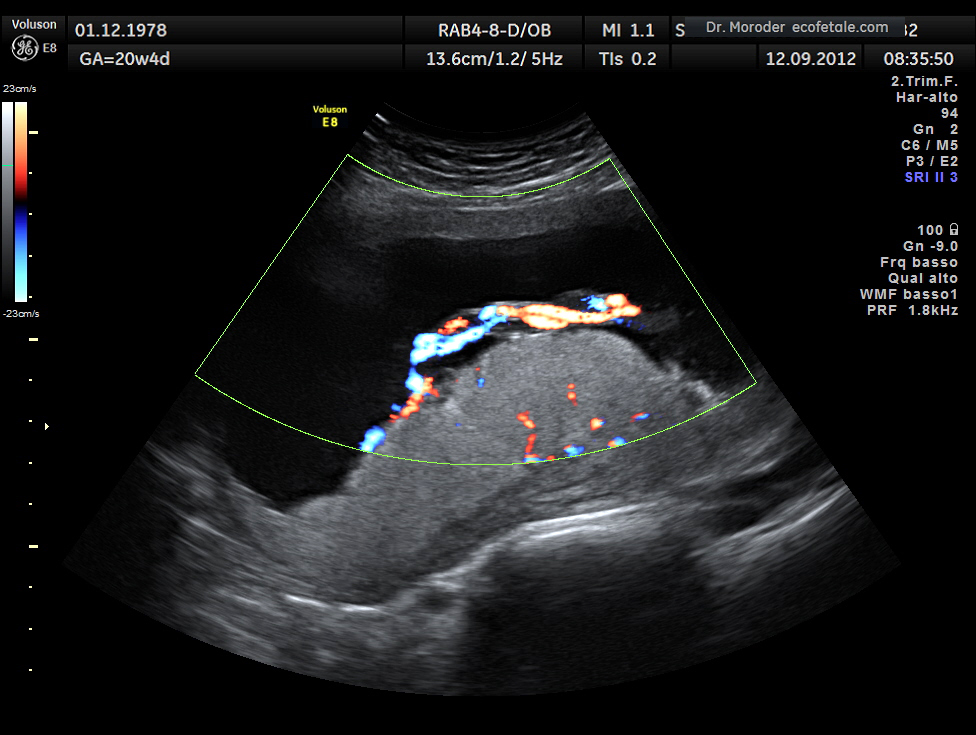

La placenta può essere posteriore, anteriore, bassa o centrale. La placenta posteriore, sui cui concentriamo la nostra attenzione in questo articolo, in particolare, si trova sul retro dell’utero e tende verso la colonna vertebrale. Nella maggior parte dei casi, la posizione della placenta non incide negativamente sulla gravidanza né sulla possibilità di parto naturale. La sola circostanza in cui si rende necessario un parto cesareo è quella in cui la placenta è in posizione centrale e bassa. Tuttavia, conoscere la posizione della placenta risulta importante soprattutto al momento di sottoporsi ad alcuni esami, tra cui l’amniocentesi. In questo caso, la placenta anteriore aumenta il rischio di passaggio di globuli rossi fetali nella circolazione sanguigna della madre.

In caso di placenta posteriore, invece, l’amniocentesi non comporta particolari rischi. Inoltre, questa condizione avvantaggia anche l’altro importante esame di diagnostica prenatale, la villocentesi. Quando la placenta è anteriore, l’esame in questione richiede l’inserimento di un ago guida, a cui si aggiungono altri due aghi. Quando la placenta è posteriore, al contrario, ci sarà bisogno soltanto di un ago per raggiungere il piatto coriale e di un altro per il prelievo dei villi. Il rischio di aborto spontaneo, in questo modo, risulta ridotto di ben tre punti percentuali